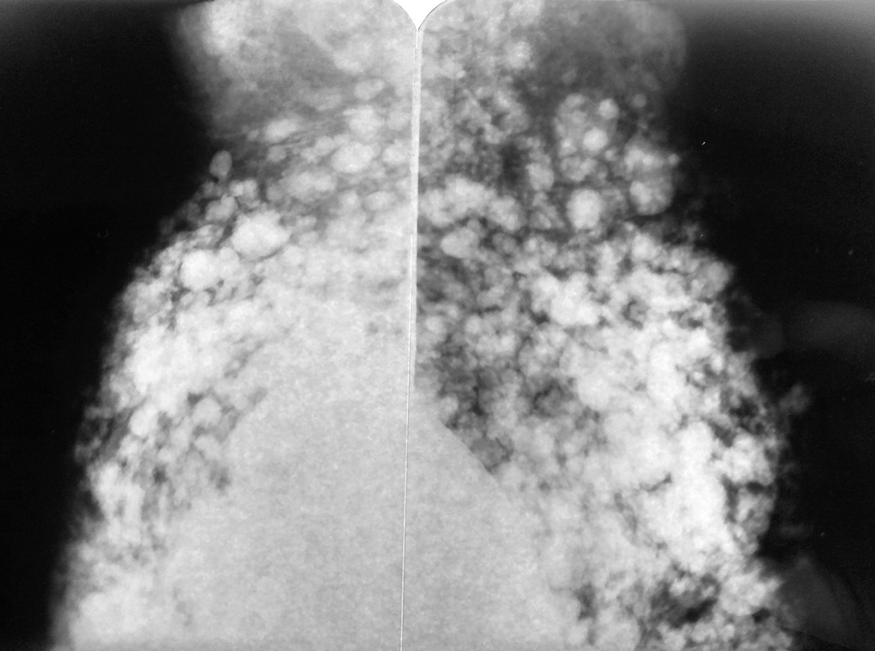

Silicones in the axilla. Mammography showing silicone in the axilla. Bilateral mammography is observed in an oblique view, in breasts with prosthetic implants from which there is abundant silicone that not only spread through the breast but also migrated to the axilla

Silicone in the axilla. Mammography showing more detail of the axillary region. Note that a large part of the axilla is filled with silicone

Silicone in the axilla. The lower axillary region is already affected by the migration of silicone

Silicone in the axilla. Mammogram where opacities are seen as a result of the past injection of silicone